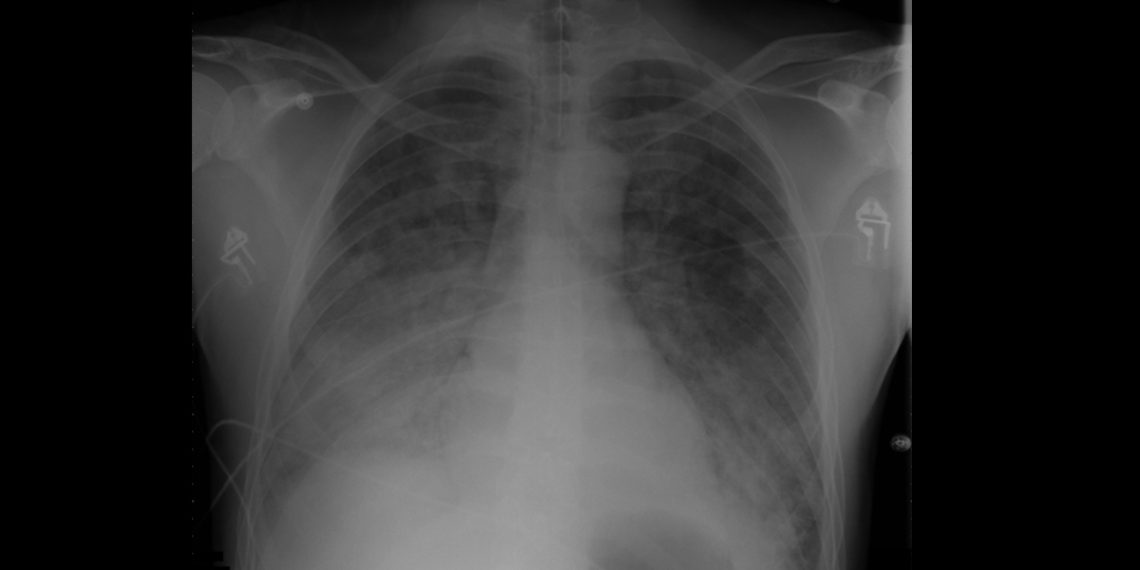

- Chest X-rays showing “white-out” appearance of fluid-filled lungs